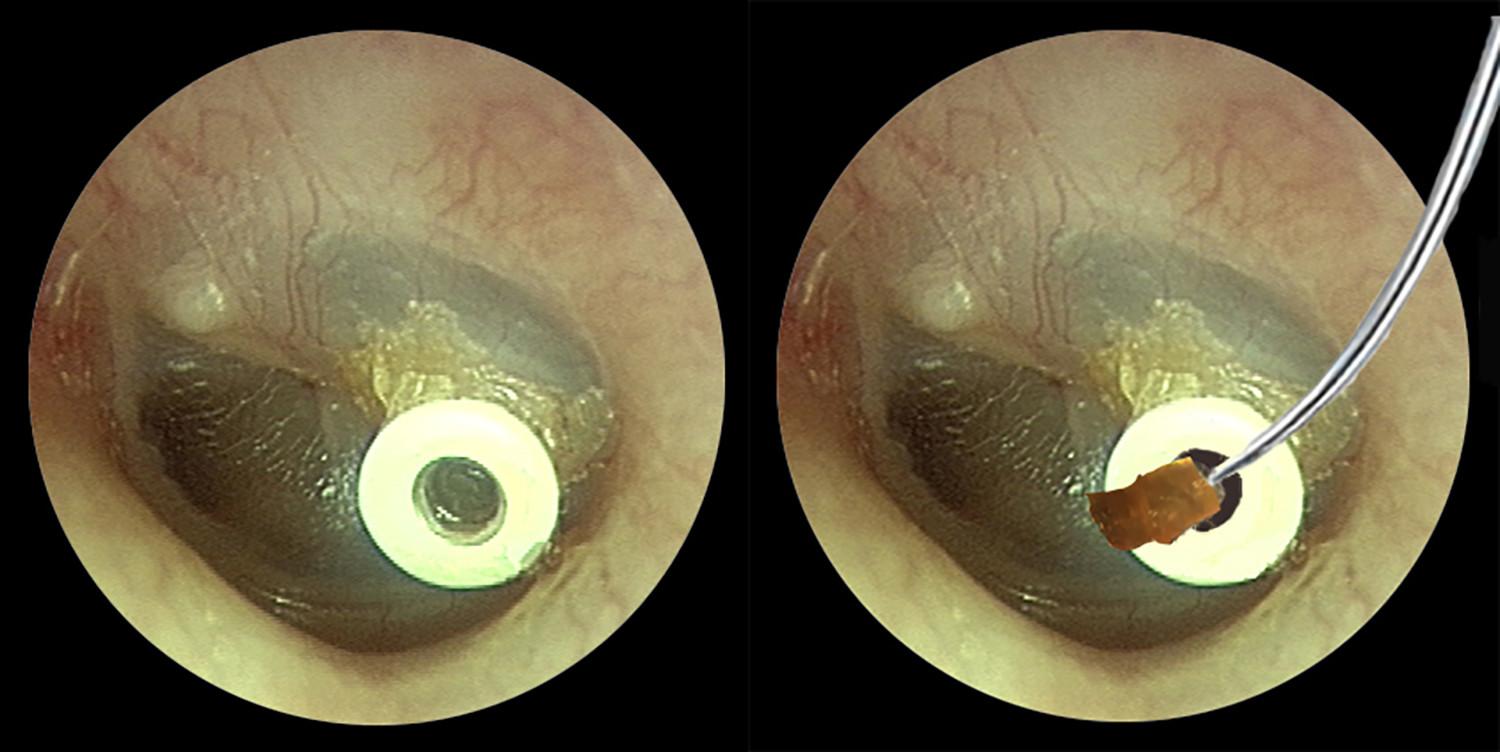

FV đã triển khai kỹ thuật tiêm xuyên nhĩ phục hồi thính lực cho các trường hợp điếc đột ngột và một số chỉ định đặc biệt. Quy trình được thực hiện dưới phương pháp nội soi, chỉ định liều và lịch tiêm theo tiêu chuẩn, với yêu cầu theo dõi chặt chẽ sau thủ thuật. Báo cáo nội bộ và các bài viết truyền thông về kết quả lâm sàng cho thấy tỉ lệ cải thiện rõ rệt ở nhiều bệnh nhân sau một liệu trình.

Điển hình là trường hợp cậu bé 9 tuổi tên NTV bỗng nhiên mất thính lực tai trái (khoảng 70 – 80 dB), gần mức điếc sâu chỉ sau một đêm. Gia đình lo lắng đưa bé đến FV và được TS.BS. Võ Công Minh chẩn đoán là điếc đột ngột vô căn. Không để mất cơ hội vàng phục hồi, bác sĩ Minh chỉ định tiêm Dexamethasone trực tiếp qua màng nhĩ vào tai giữa.

Quy trình kỹ thuật tinh tế:

- Ủ tê cục bộ trong 20-25 phút;

- Tiêm dưới hướng dẫn nội soi để đảm bảo độ chính xác;

- Sau tiêm, bé cần giữ yên tư thế 20 phút, tránh nói hay nuốt để tối ưu hấp thu;

- Mỗi lần tiêm cùng chuẩn bị và hồi phục mất khoảng 45 – 50 phút, bé được cho về ngay, không cần nhập viện.

Liệu trình gồm 5 mũi, cách nhau mỗi 2 ngày. Sau mũi thứ 3, thính lực của bé đã cải thiện; chỉ sau 3 tháng, thính lực gần như về mức bình thường, chỉ còn giảm khoảng 10 dB. Gia đình và đội ngũ y bác sĩ đều vui mừng khi chứng kiến kết quả này.

Phương pháp tiêm xuyên nhĩ là một trong những cách điều trị hiệu quả trong nhóm điếc đột ngột; mũi tiêm steroid tác động trực tiếp tại nơi cần thiết, giúp giảm viêm nhanh và phục hồi thính lực trong thời gian vàng (trước khi tổn thương tai trở nên không thể hồi phục). Rất đáng lưu ý, FV là một trong số rất ít cơ sở tại Việt Nam áp dụng kỹ thuật này ngoại trú cho trẻ em.